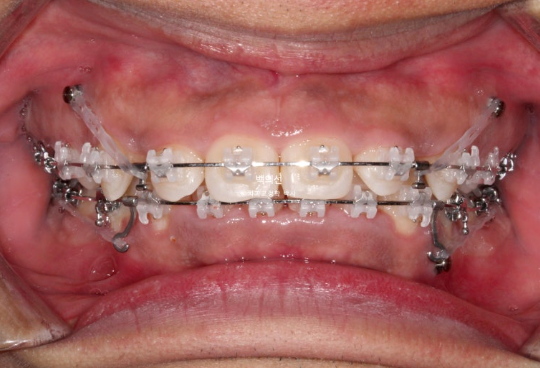

2년 전 교정치료를 이어받기 위해 오신 외국인 환자분입니다.

외국에서 발치교정 진행 중 브라켓을 붙인 채로 치료 도중 오셨으며 한국에 머무르게 되어 치료 마무리를 위해 오셨습니다.

사진은 브라켓을 뗀 후 사진이고, 위 앞니가 아랫니를 많이 덮는 과개교합이 보입니다.

아랫니가 안 보일 정도의 심한 과개교합 입니다.

위 아래 발치공간이 절반 이상 남아있는 상황입니다.

클리피씨 장치 부착하고 치료를 시작합니다.